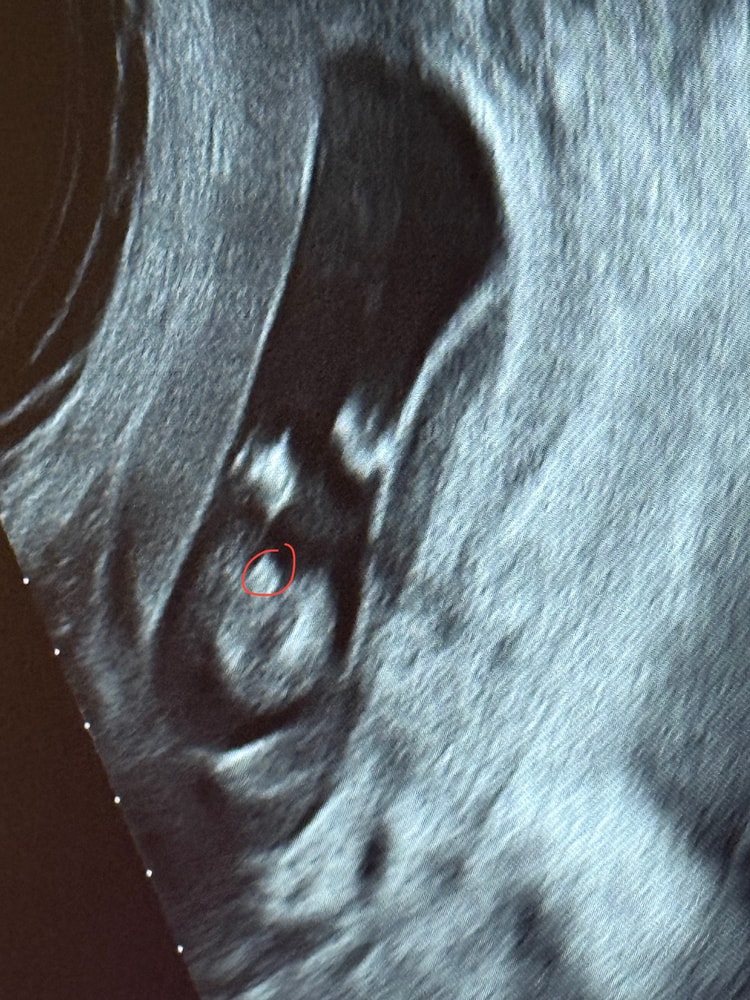

Маша, ну у вас по-моему это не пуповина, с первым сыном у нас писюн такой же был на экране, а в эту беременность вот так и то что я обвела зеленым меня смущает ибо узистка утверждала, что то, что обведено красным это писюн, но по-моему это как раз пуповина в срезе😅 Изображение Изображение Изображение

09.11.2025

Маша, яичники это,а у мальчиков помимо этого ещё пипка торчит)

Маша, пипка прям пипка, палочка.

Маша, примеры Изображение Примеры из интернета,мне кажется ваш случай девочка Изображение